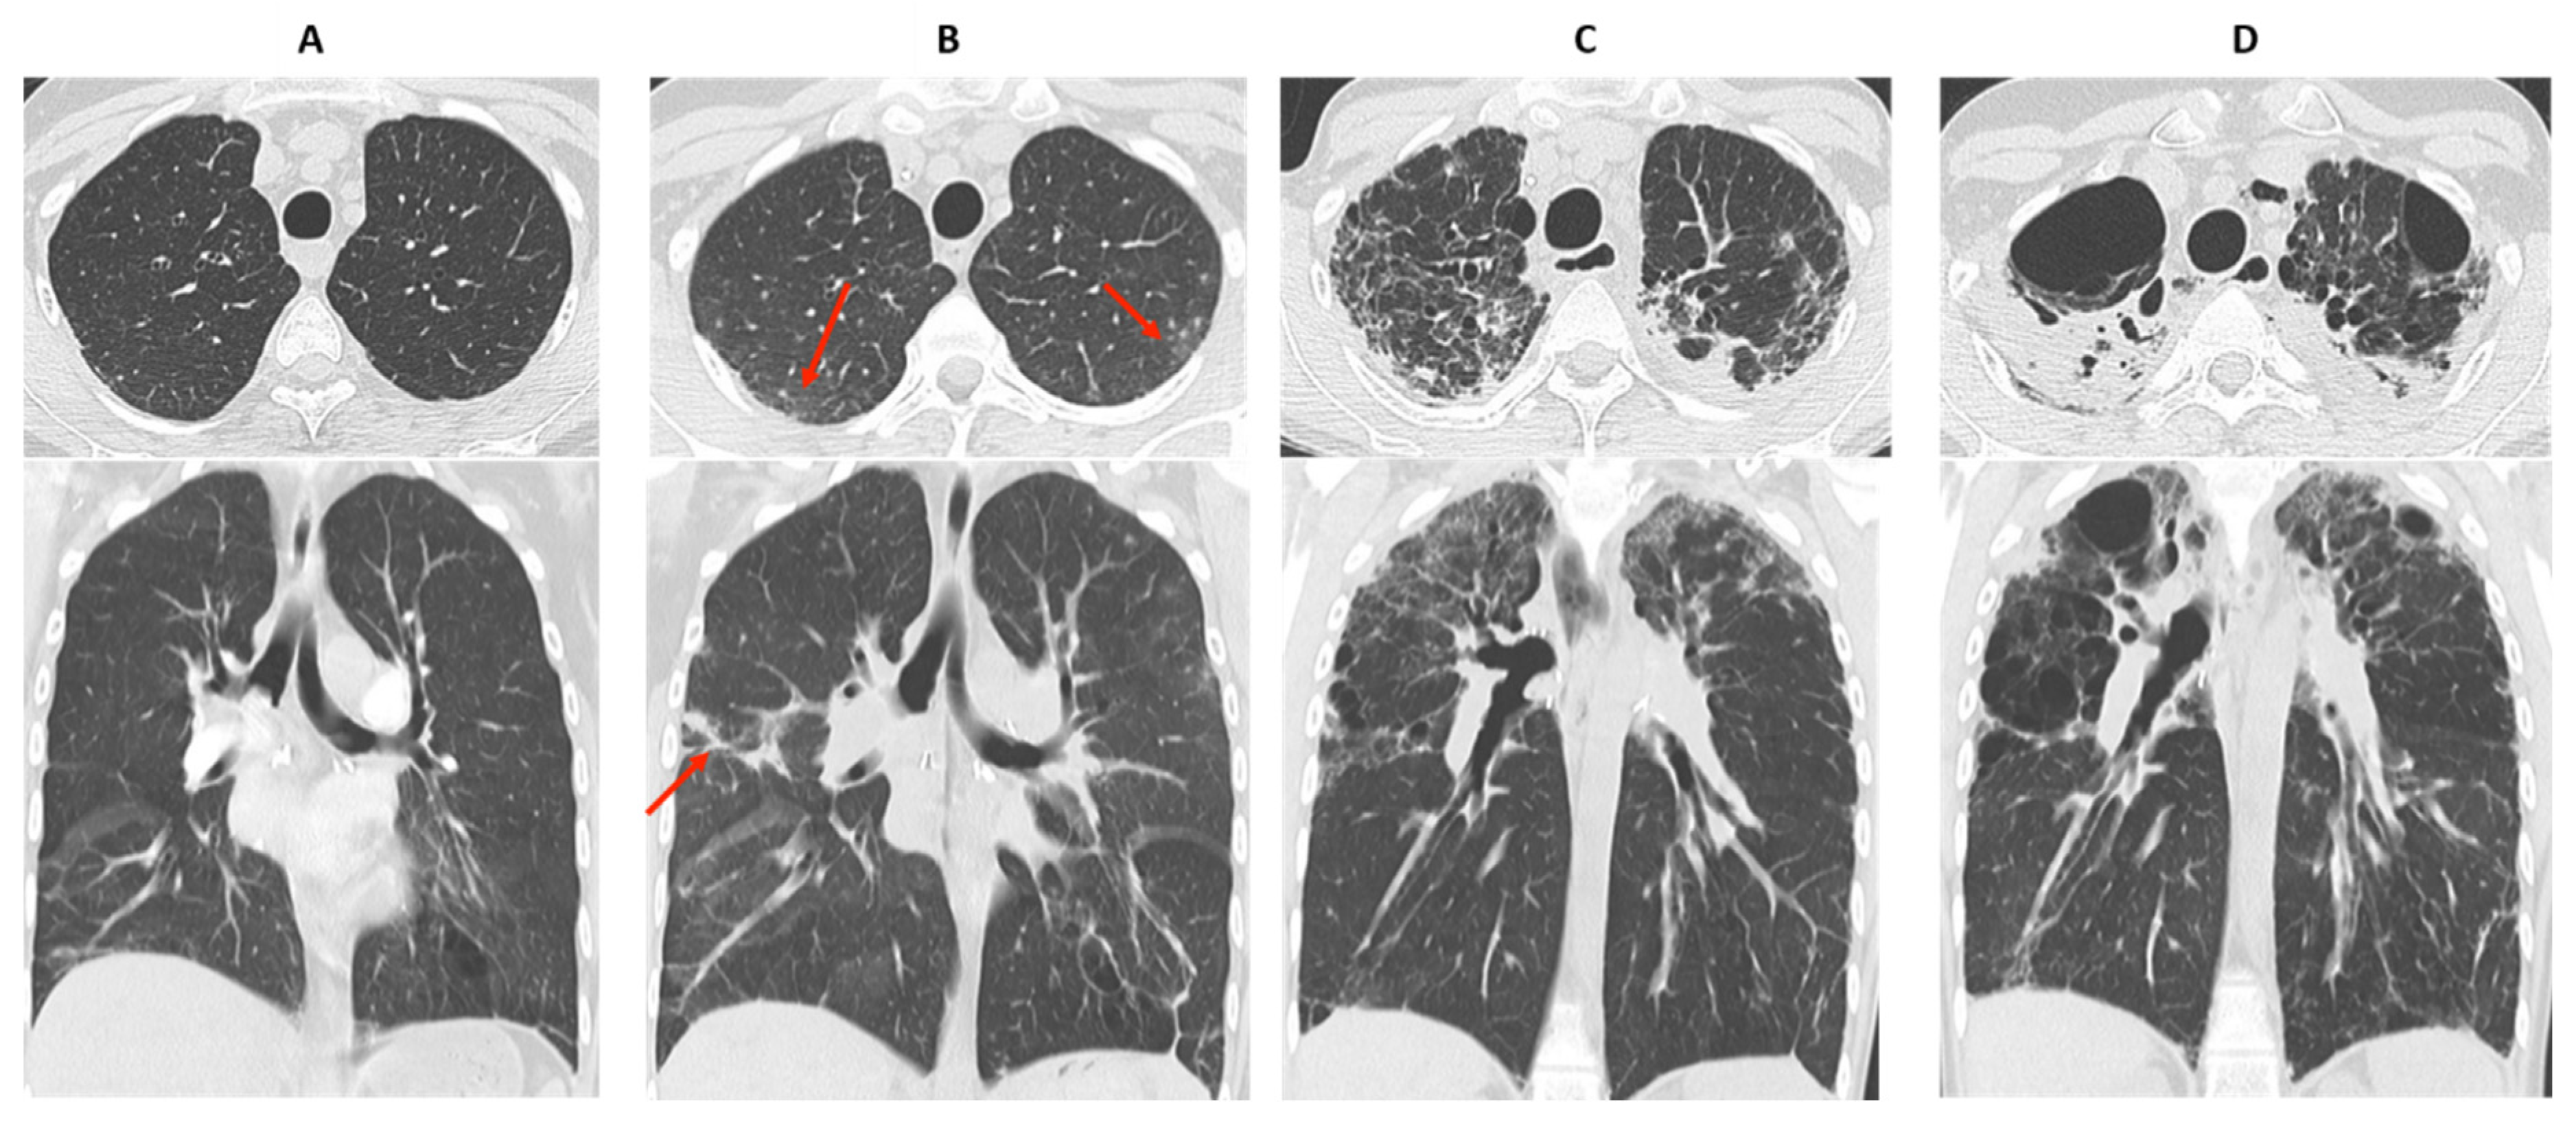

4. Bronchiolitis Obliterans Syndrome

5. Restrictive Allograft Syndrome (RAS)

6. Overlap BOS/RAS: Mixed-Phenotype CLAD